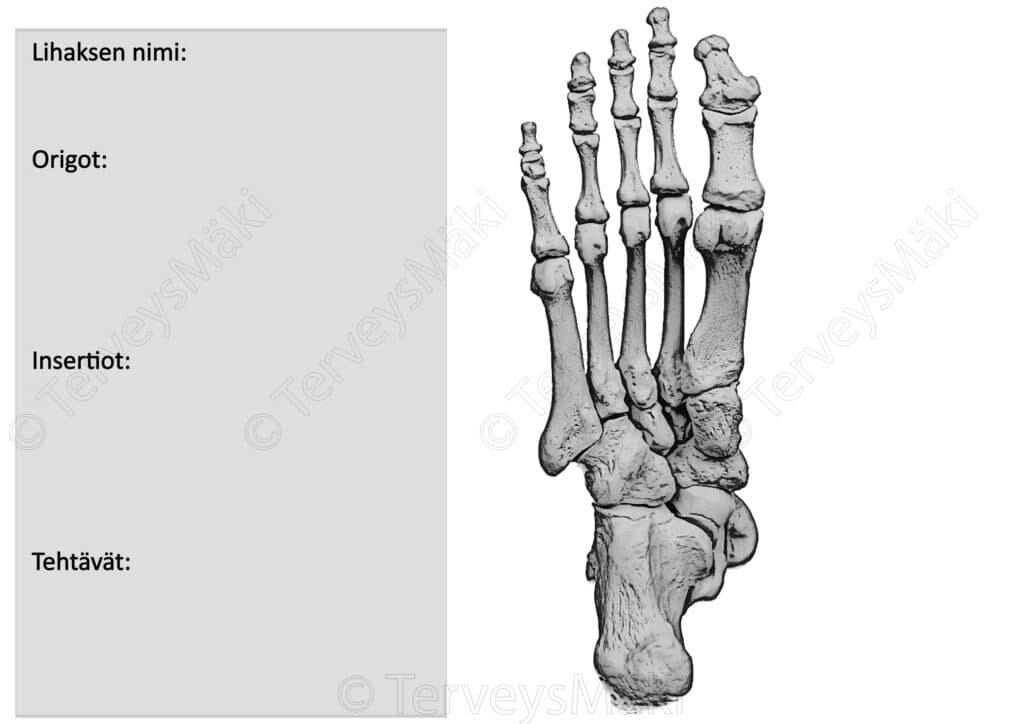

Kuva flexor digitorum brevis lihaksen lähtökohdat & kiinnityskohdat

Voit vapaasti tallentaa ja tulostaa alla olevan kuvan.

- Väritä kuvan luupohjaan lihaksen lähtö- ja kiinnityskohdat.

- Piirrä kyseessä olevan lihaksen lihasrunko.

- Kirjoita oheiseen pohjaan:

- Lihaksen nimi suomeksi ja latinaksi.

- Lihaksen lähtö- ja kiinnityskohdat suomeksi ja latinaksi.

- Lihaksen tehtävät.